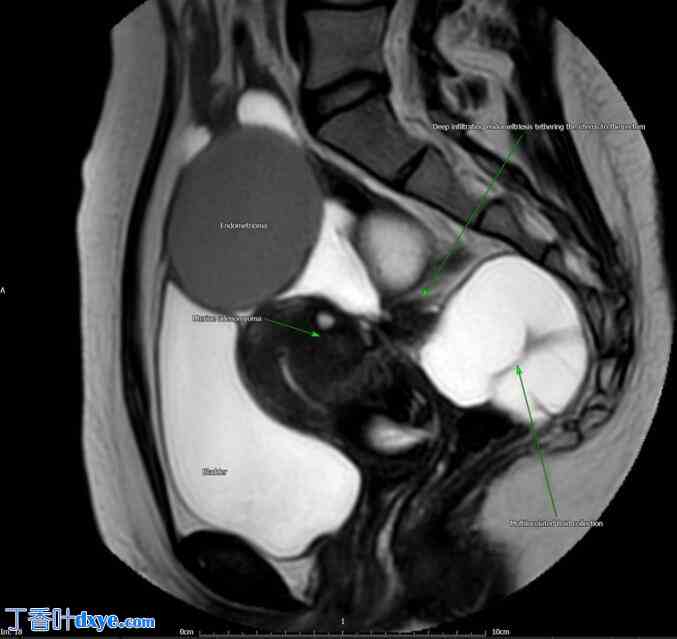

磁共振成像 (MRI) 显示盆腔内多发清晰的囊性结构、子宫腺肌病、双侧子宫内膜异位症以及子宫与直肠乙状结肠后连接处粘连(图1、图2)。由于影像学检查结果与子宫内膜异位症的诊断并不完全一致,因此进行了诊断性腹腔镜检查。

图 1.

经中部骨盆的 T2 矢状面磁共振图像。子宫内膜异位症灶性大面积,并通过深部浸润性子宫内膜异位症与直肠相连。子宫后方可见多房积液,经组织学证实为间皮瘤。膀胱和宫底前方可见一单独的子宫内膜异位瘤。